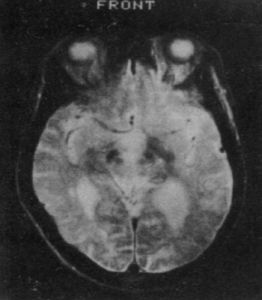

②血管性:多發性腦梗死病史、假性球麻痹、腱反射亢進、病理征和神經影響學檢查等可提供證據;

④血及腦脊液常規檢查無異常,CT、MRI檢查也無特徵性所見。